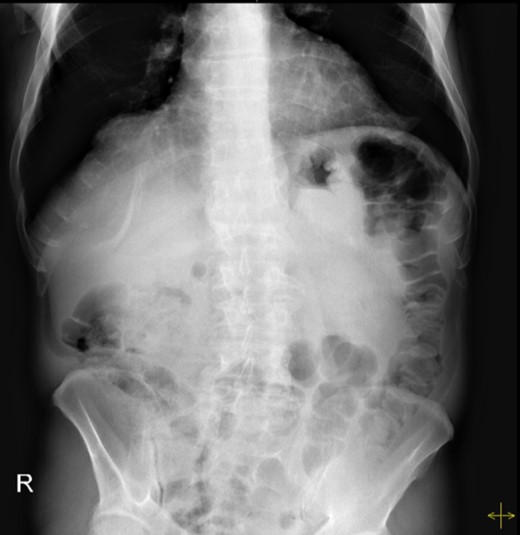

An upper endoscopy was performed, revealing a severe esophagitis with a distortion of the gastric anatomy. A great amount of stasis fluid and multiple ulcerations of the gastric fundus were present. An upper gastrointestinal series was also performed, revealing an inverted stomach, with the atrum being positioned superiorly to the fundus, with an abnormal position of the pylorus (Fig. 2).

Upper gastrointestinal series, revealing an inverted stomach, with the atrum being positioned superiorly to the fundus and a stretched duodenal arch, with an abnormal position of the pylorus.